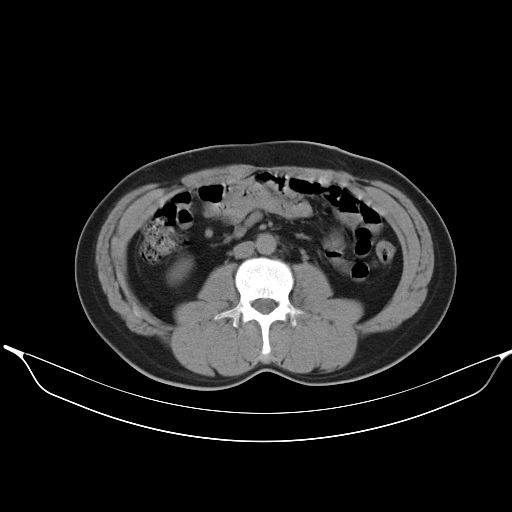

标题: CT25490:男,40岁,体检发现;无其它不适。 [打印本页]

标题: CT25490:男,40岁,体检发现;无其它不适。

2、轻度脂肪肝。

1、均为转移,原发灶不在肺内。2、肺癌肺转移。